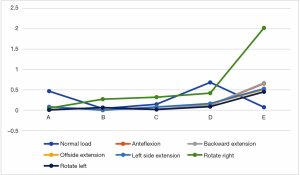

Under each working condition, as the defect volume increased, the stress differences between consecutive groups were as listed in Table 4.

Full table

We used the data to generate a dot plot to more intuitively show the relationship between the defect volume and the increase in stress (Figure 14).

The 5/5 defect in the anterior column of the injured vertebra was a simulated extreme condition that does not exist in actual clinical practice, so we removed this condition from consideration. According to the chart, after the implantation of the internal fixator, the stress increased significantly when the injured vertebra showed a defect. As the defect volume increased, the stress increased correspondingly, and the increase in stress represented by group D (stress difference between the 3/5 defect group and the 4/5 defect group) was the greatest.